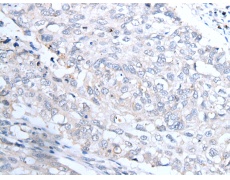

ELISA, IHC |

IHC positive control: |

Human lung cancer and human esophagus cancer |

IHC Recommend dilution: |

20-100 |